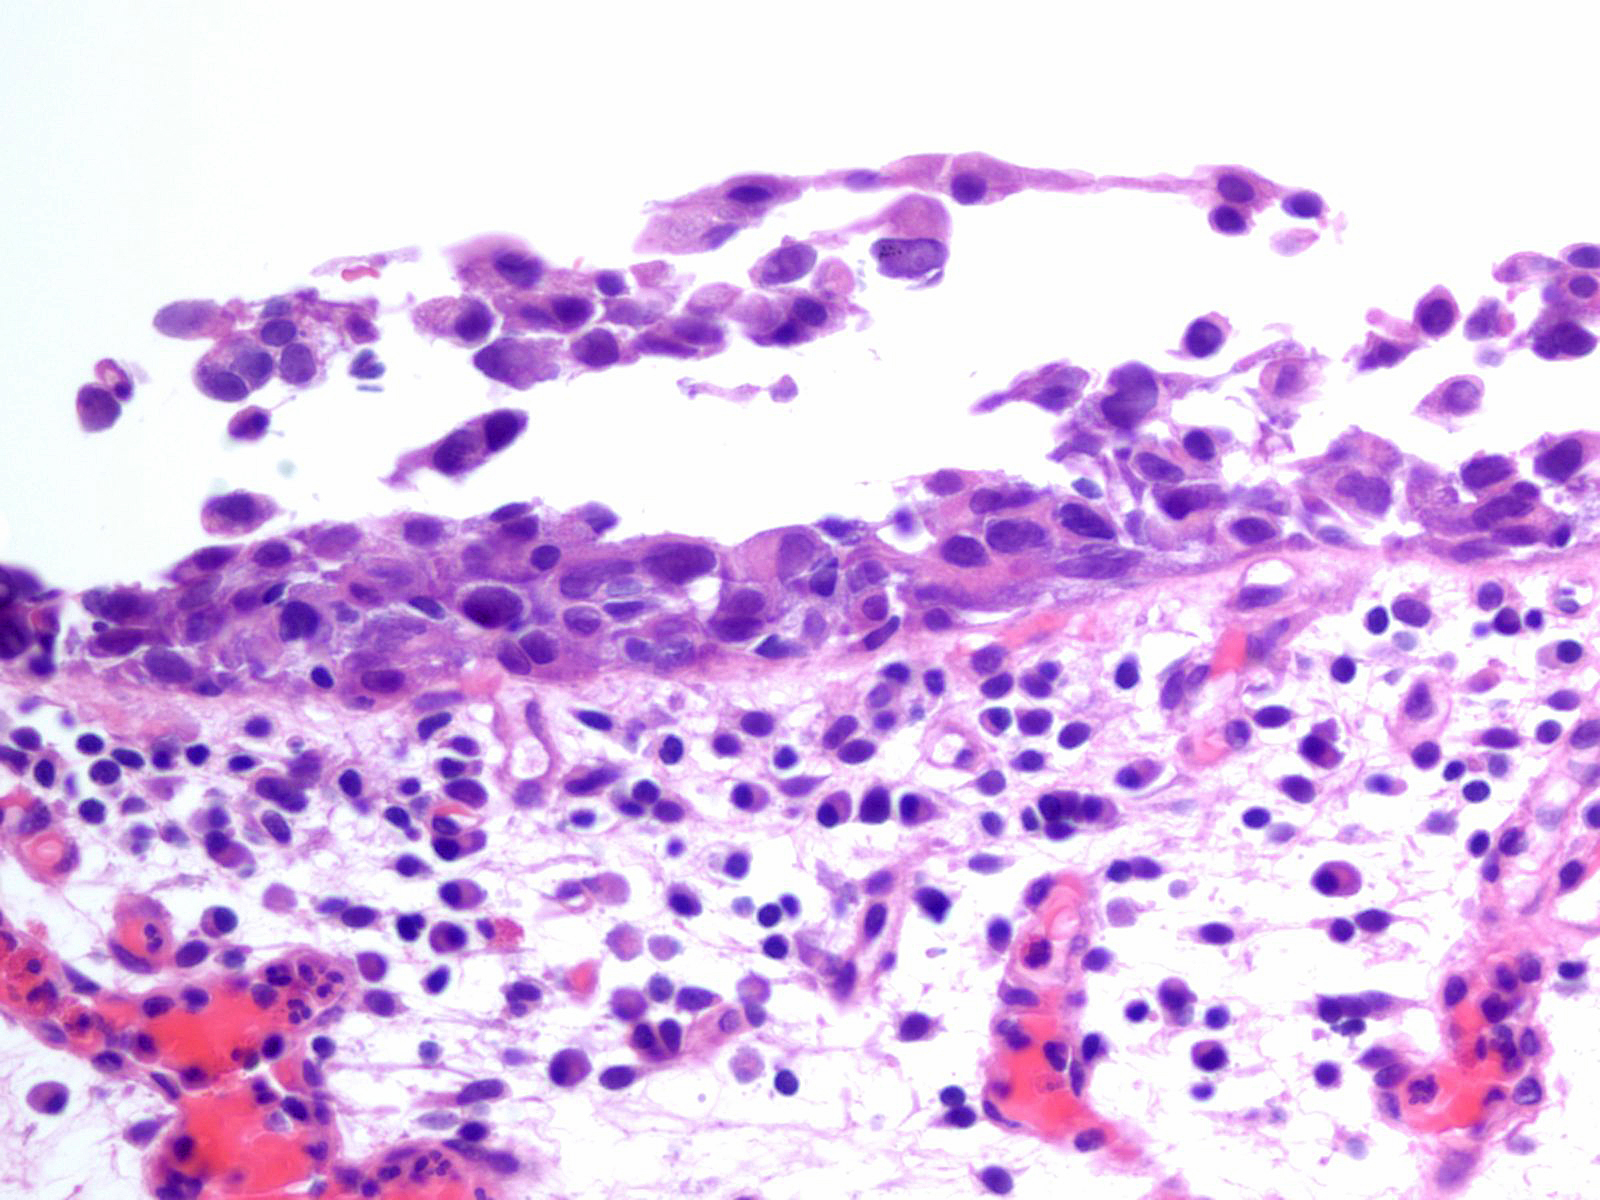

Consensus grade: Carcinoma in situ (CIS)

Lesion shows marked variation in nuclear size, shape and chromatin. Architecturally, cells appear irregularly clustered and the epithelium is disorganized.